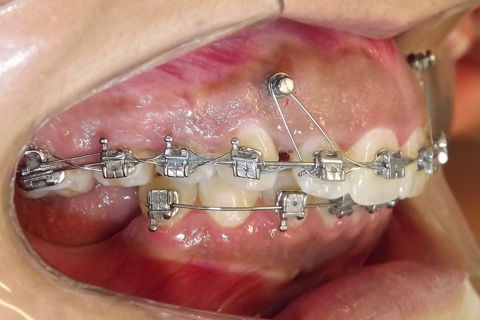

Foto após 22 meses.